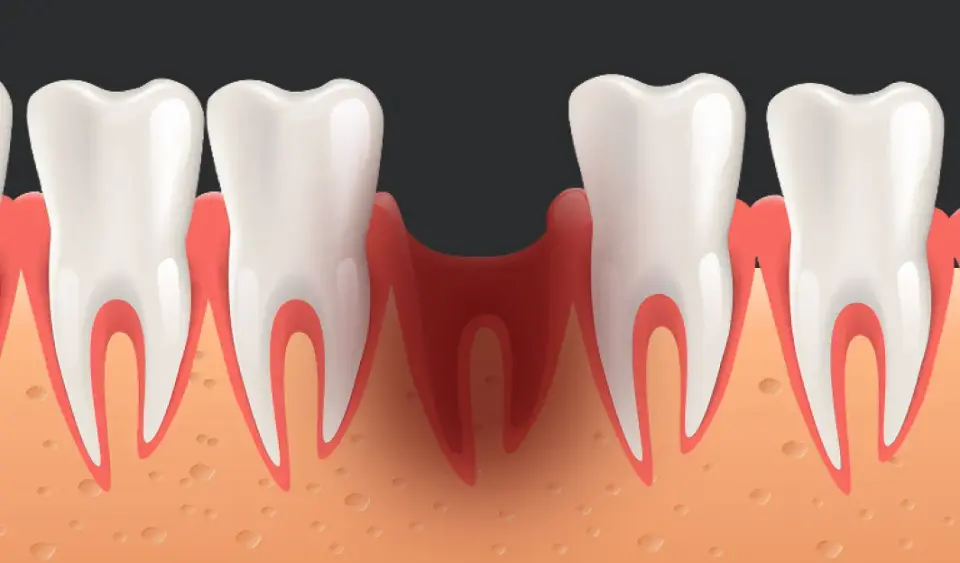

Ropień dziąsła: Jak szybko złagodzić ból i skutecznie wyleczyć?

Ropień dziąsła to ostra infekcja. Sprawdź, jak bezpiecznie złagodzić ból w domu, kiedy pilnie iść do dentysty i uniknąć groźnych powikłań.

Od czego puchną dziąsła? Poznaj przyczyny i skuteczne leczenie!

Opuchnięte dziąsła? Poznaj najczęstsze przyczyny, objawy i skuteczne metody leczenia. Sprawdź, jak sobie pomóc i kiedy iść do dentysty.

Ropa w dziąśle: Jak sobie pomóc i kiedy pilnie do dentysty?

Ropa w dziąśle? Sprawdź domowe sposoby na ulgę i leki bez recepty. Dowiedz się, czego unikać i kiedy pilnie do dentysty, by uniknąć powikłań.